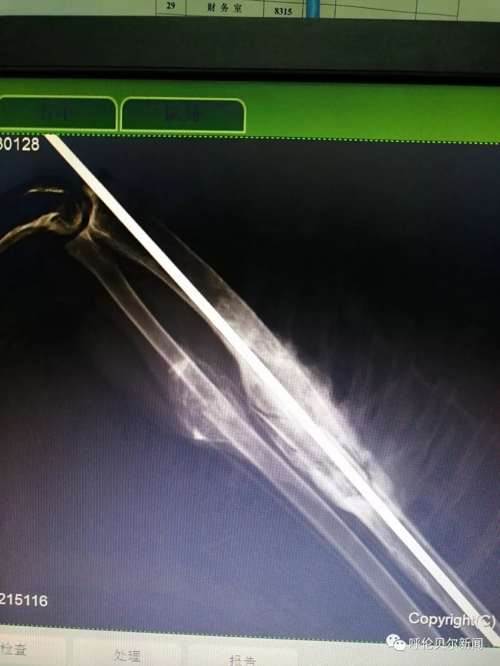

双龙还给雕鸮换了一处居所,在镇区东部新村的大仓库内,“这仓库里有房架子,雕鸮可以飞到高处休息,像在林子里一样。“这家伙很聪明,第一次在大房子里飞的时候撞在窗玻璃上,第二次它就能够稳稳地站在窗台上了。”双龙夸讲雕鸮时的表情像在夸讲自己的孩子。 >>>2019年3月15日 雕鸮活动在人迹罕到的偏僻之地,通常远离人群,属于夜行性猛禽,以各种鼠类为主要食物,被誉为“捕鼠专家”,也吃兔类、蛙、刺猬、昆虫、雉鸡和其他鸟类。然而,被救的这只雕鸮却在过去的203天里,与人类亲密接触。双龙的蒙语,许是它神经条件反射的反射弧,许是它渐渐感受到的源自人类的善意。3月15日上午,双龙带着雕鸮到新右旗人民医院拍了放飞前的最后一张X光片,无需挂号,一路绿色通道。医生告诉双龙骨头断裂处已长出骨甲,恢复得特别好。“你看,你看,这是你的翅膀,你痊愈啦,就该回 家了!”在医院的电脑前,双龙依旧用哝哝软软的蒙语与雕鸮交流……